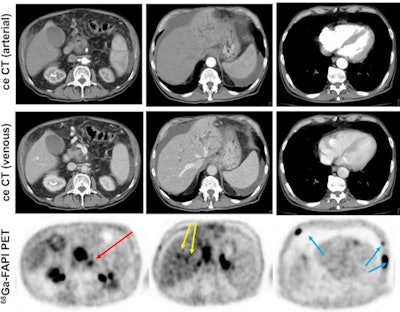

PDAC consists of cancer cells that express fibroblast activation protein (FAP). By adding a FAP inhibitor (FAPI) labeled with gallium-68 to PET/CT imaging, more than half of the PDAC patients in this study had their cancer more accurately staged or restaged, compared with results from contrast-enhanced CT.

The researchers found that Ga-68-FAPI-PET/CT provided new TNM findings for 10 of 19 PDAC patients (53%), which included the upstaging of eight of 12 patients (67%) with recurrent or progressive disease, while one patient's (8%) recurrent or progressive cancer was downgraded. Among seven PADC patients with primary disease, one case out of seven (14%) was upstaged; no patients were downstaged.

"In all cases, changes in staging were caused by the detection of new or additional distant metastases in one or more organ systems," the authors added. They also found a "markedly elevated uptake" of Ga-68-FAPI in most PDAC patients as soon as one hour after administration.

The findings suggest that Ga-68-FAPI- PET/CT is a "promising new imaging modality in staging of PDAC that may help to detect new or clarify inconclusive results obtained by standard CT-imaging," Röhrich and colleagues concluded.

"Analyses of tracer biodistribution demonstrated a high FAPI uptake in primary PDAC as well as lymph nodes and distant metastases, whereas healthy tissues have negligible background activity," they wrote. "This leads to excellent tumor/background ratios for PDAC, similar to those shown by previous studies on FAPI-PET/CT in PDAC and other tumors."